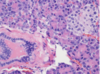

Esophagus

Epithelium of the esophagus is made of what type of cell

Squamous

Esophagus